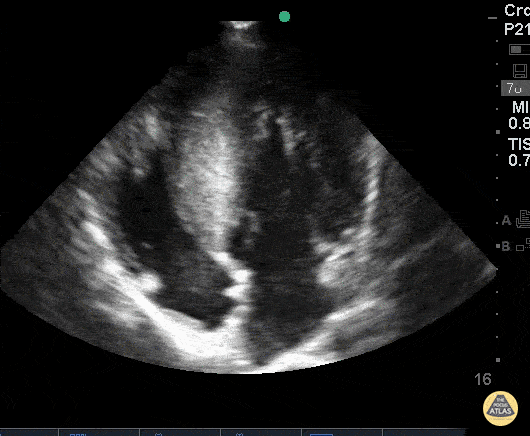

Pediatrics - HOCM - Hypertrophic Obstructive Cardiomyopathy

19 y/o came in after a syncopal episode playing video games. Got defibrillated in the field Vfib rate 200s. Bedside echo demonstrated global LVH with septal predominant thickening consistent with HOCM. Father has a history of ICD of “heart condition.” Dr. Dustin Morrow